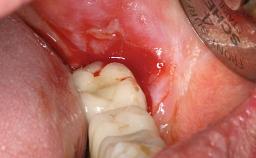

Excess Cement Resulting in Peri-implant Infection Presenting as a Draining Sinus Tract

Biological complications caused by undetected cement residue have been receiving much attention. Excess cement might be responsible not only for rapidly developing of peri-implantitis, but also for delayed or chronic manifestations of the disease many years after cementation (Wilson 2009; Linkevicius and coworkers 2013). Invitro and clinical studies have shown that it is very difficult or even impossible to completely clean up excess cement at subgingival margins, so popular in cemented restorations (Agar and coworkers 1997; Linkevicius and coworkers 2011, 2012). Possible outcomes of biological complications due to excess cement range from temporary inflammation of the peri-implant soft tissues without any serious esthetic and functional consequences all the way to implant loss. This report describes a case of peri-implantitis caused by residual cement; as well as the management and quite unusual resolution of the complication. The patient presented in 2009 with a draining sinus tract, tenderness on chewing, and tissue contact above the implant-supported restoration. The implant had been restored approximately three years before.